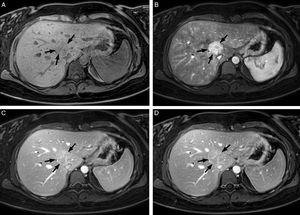

Mujer de 25 años con ictericia y colestasis. La RM hepática, secuencia T1-TEG con supresión de grasa (a) sin contraste y poscontraste (b) en fase arterial, portal (c) y equilibrio (d), demuestra una masa de 36mm en el segmento VIII (flechas), bien delimitada, con realce intenso y heterogéneo, con centro hipointenso en la fase arterial, que en las fases portal y de equilibrio se hace mayoritariamente isointensa con alguna zona central que permanece hiperintensa, en relación con hiperplasia nodular focal.

RM: resonancia magnética; TEG: turbo eco de gradiente.